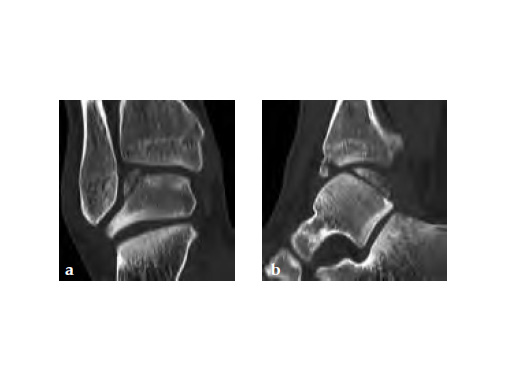

Fig 1ab Preoperative AP and lateral x-rays.

A 20-year-old construction worker fell from a 3 m height. He sustained a typical posterolateral impression and flake fracture of the talar dome.